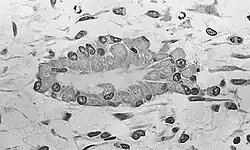

Osteoblastos (do grego ὀστέο-,"osso", e βλαστάνω, "germinar") são as células provenientes das células osteoprogenitoras, são responsáveis pela síntese dos componentes orgânicos da matriz óssea, colágeno, proteoglicanos, glicoproteínas. Os Osteoblastos localizam-se na superfície do osso, formando lâminas de células cuboides a colunares.

Quando estão em intensa atividade sintética, suas formas modificam-se, lembrando um cubo, com citoplasma tornando-se mais basófilo. Em estado pouco ativo tornam-se achatados e a basofilia citoplasmática diminui. Uma vez aprisionado pela matriz óssea recém sintetizada, o osteoblasto recebe o nome de osteócito. A matriz deposita-se em redor da célula e dos seus prolongamentos, formando assim as lacunas e os canalículos (Canais de Havers). Quando os Osteoblastos entram em estado de quiescência, deixam de produzir a matriz, se tornando células de revestimento ósseo.